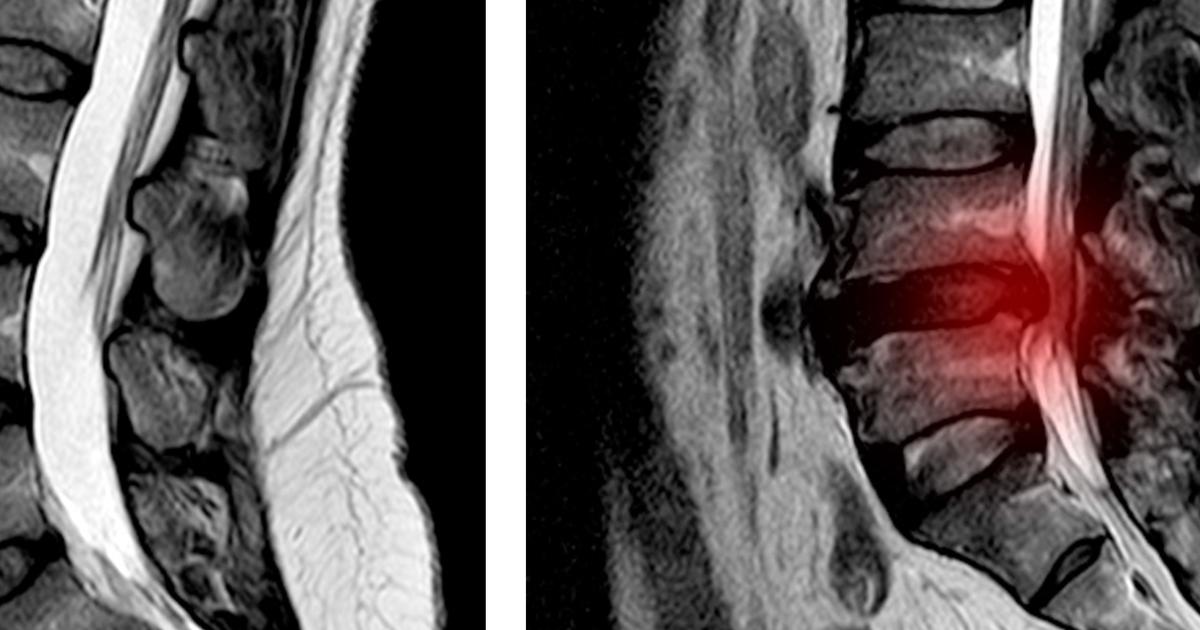

Spinal cord injury describes any damage that occurs to any region of the spinal cord or the lower spinal canal nerves. Spinal cord injuries can permanently alter an affected individual's sensations, strength, and any other functions of their body that involve nerves located underneath the site of their injury. General symptoms that occur with a spinal cord injury include movement loss, sensation loss, abnormal sensations, bladder or bowel incontinence, pain, breathing difficulty, exaggerated reflexes, and changes in sexual function. Most spinal cord injuries are the result of motor vehicle accidents, violence, sports, disease, alcohol, and falls. Diagnosis of a spinal cord injury can be made using X-rays, CT scans, and MRI. Treatment revolves around improving quality of life and preventing further injury since there is no way to reverse spinal cord damage.

A lumbar spinal cord injury occurs when an individual incurs damage to the section of their spinal cord that controls and influences their legs and hips. The lumbar spinal cord region is located underneath the cervical and thoracic spine. The nerves that control communication between an individual's legs and brain are found in their lumbar spine. Unlike the other sections of the spine, only the L1 and L2 levels of the lumbar section actually contain spinal cord tissue. Injuries that occur at the L3 to L5 levels occur to the nerve roots instead of the spinal cord. Injuries that impact the lumbar spinal cord cause dysfunction in the grain, hips, thighs, and abdominal muscles. Lumbar spinal cord injuries may result in the need for the part or full-time use of a wheelchair, the need for walking devices or braces to mobilize, paraplegia with functional independence, lack of bladder control, and lack of bowel control. If the injury is limited to the lumbar spinal cord, the patient should retain all of their upper-body mobility and strength. Except for requiring the use of a wheelchair or walking equipment, patients who experience a lumbar spinal cord injury live reasonably normal lives.